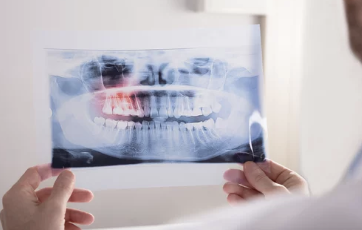

- 치과 상담: X-ray 촬영으로 사랑니의 위치, 매복 상태, 주변 신경과의 관계를 확인합니다.